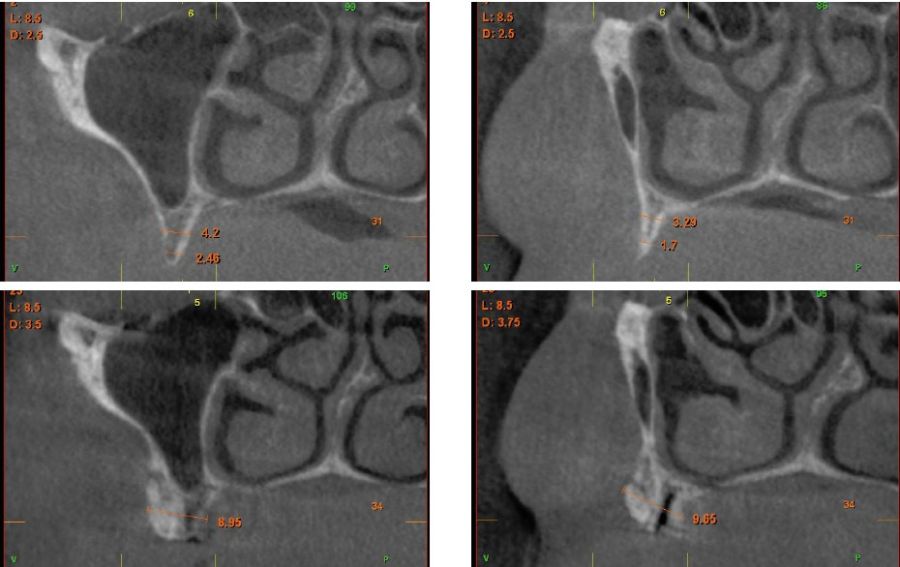

Fueron reclutados pacientes de forma retrospectiva con atrofia ósea horizontal severa (con anchura residual de cresta menor o igual a 3 mm), donde se colocasen injertos en bloque para regeneración ósea y posteriormente se insertarán implantes, con un tiempo de seguimiento tras la carga mayor o igual a 10 años. Antes de la colocación de los implantes, todos los pacientes fueron sometidos a una evaluación integral que incluyó modelos diagnósticos, un examen clínico intraoral detallado y un estudio tomográfico mediante Cone beam (TAC dental). Las imágenes obtenidas fueron analizadas con un software especializado (BTI-Scan III) para garantizar una planificación tridimensional precisa. Posteriormente, se llevó a cabo un encerado diagnóstico que sirvió como base para la creación de una guía quirúrgica, optimizando la ejecución de la rehabilitación planificada. La posición final de los dientes obtenida del encerado será la que guíe el proceso de regeneración para lograr el volumen óseo necesario para colocar los implantes en la posición necesaria. Antes de la inserción de los implantes se utilizó una pre-medicación antibiótica consistente en amoxicilina 2gr vía oral una hora antes de la intervención y paracetamol 1 gramo vía oral (como analgésico). Posteriormente los pacientes prosiguieron con un tratamiento de amoxicilina 500-750 mg vía oral cada 8 horas (según peso) durante 5 días. Todos los injertos se obtuvieron de rama mandibular y fueron divididos en cortical y esponjosa, según la técnica de Khoury18. Se conservaron en PRGF-Endoret hasta el momento de su uso y el hueso particulado obtenido de la parte medular del injerto se colocó embebido en PRGF-Endoret fracción 2 sin activar. Una vez posicionados los injertos fueron fijados mediante material de ostesíntesis (KTOÒ– Biotechnology institute) y toda la zona intervenida se cubre con membranas de fibrina autóloga (PRGF-Endoret fracción 1 activada y retraída) antes de la sutura con monofilamento de 5/0 para lograr cierre primario. Los injertos maduran 4-5 meses y posteriormente se realiza un nuevo Cone beam para conocer la anchura lograda y planificar la inserción de los implantes. La inserción de los implantes fue realizada por un mismo cirujano, mediante la técnica de fresado biológico, a bajas revoluciones, sin irrigación26-28. Una vez transcurridos cuatro meses desde la inserción de los implantes, se lleva a cabo la carga de los mismos mediante una prótesis provisional de carga progresiva elaborada en resina, con estructura metálica de barras preformadas y atornillada a transepiteliales. Estas prótesis provisionales se mantienen de 3 a 6 meses, en función de la adaptación y requerimientos de cada paciente. Una vez transcurrido este tiempo se realizan las prótesis definitivas. Tras la colocación de las prótesis definitivas los pacientes entran en un programa de seguimiento al que acuden cada 6 meses. En estas visitas se realizan radiografías panorámicas de control y periapiacales en la zona de inserción de los implantes. Las radiografías periapicales se llevan a cabo con posicionador, para generar imágenes reproducibles y los pacientes son colocados para la radiografía panorámica con posicionador fijo en glabela y mentón, mordedor para zona interincisal con eje de línea media, plano bipupilar y frackfort (marca láser) y con los pies sobre marcas trazadas en el suelo, con el propósito de que sean altamente reproducibles los resultados. Sobre estas radiografías se llevan a cabo las mediciones necesarias para comprobar la estabilidad y pérdida ósea crestal de los implantes. Una vez obtenida la radiografía en formato digital es calibrada mediante un software específico (ImageJ) a través de una longitud conocida como es el implante dental. Una vez introducimos la medida de calibración, el programa informático realiza un cálculo basado en esta medida para eliminar la magnificación, pudiendo realizar mediciones lineales exentas de este error. En la visita final de seguimiento (10 años) se lleva a cabo un nuevo cone-beam para estimar la anchura ósea final tras el período de carga de los implantes y valorar la potencial reabsorción del volumen óseo logrado con la técnica regenerativa del injerto en bloque. El paciente fue la unidad de medida para el análisis de la edad, sexo y la historia médica. La variable principal estudiada ha sido el mantenimiento del volumen óseo logrado con la técnica regenerativa tras 10 años de carga. Como variables secundarias se han estudiado la supervivencia de los implantes y la pérdida ósea mesial y distal. La supervivencia de los implantes se calculó mediante el método de Kaplan-Meier. Los datos fueron analizados con SPSS v15.0 para windows (SPSS Inc., Chicago, IL, USA). Fue realizado un test de shapiro-Wilk sobre los datos obtenidos para constatar la distribución normal de la muestra.

La media de la pérdida ósea mesial de los implantes estudiados en el final del período de seguimiento a los 10 años fue de 0,94mm (+/- 0,28) mientras que la media de la pérdida ósea distal fue de 0,77 mm (+/- 0,17). Durante el tiempo de seguimiento no se registró ningún fracaso en los implantes estudiados. La media de la anchura ósea a los 10 años fue de 6,26 mm (+/- 1,08). En la figura 4 se observa la diferencia entre la anchura inicial, la lograda tras la consolidación del injerto y tras los 10 años de seguimiento. En las figuras 5-19 se muestra uno de los casos incluidos en el estudio.